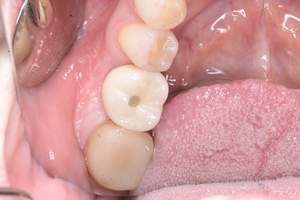

症例写真-1

- Befor

- After

症例写真-2

- 途中経過

| 年齢 | 50代・男性 |

| 主訴 | 右下歯が疼く |

| 治療内容 | ・右下6番インプラント ※1:FGG(遊離歯肉移植術)とは、足りない歯ぐきを上顎から上皮を切り取り移植する外科手術 |

| 治療費 | 合計:902,000円(税込) ■内訳 |

| 治療期間 | 9ヵ月 |

| 治療方針 | 右下の当該歯は歯根破折により保存不可能と診断しました。歯周疾患も伴っていたため抜歯後に骨吸収※1が大きく起こることが予測できました。チタンメッシュ併用骨再生誘導法(GBR※2)を選択しインプラント埋入と同時に行い自然な歯槽骨のラインを再現しました。またGBRを行う際にインプラント辺縁の付着歯肉の減少が起こる為、遊離歯肉移植術(FGG※3)を行い清掃性を考慮した形態に仕上げました。 ■治療方針の解説 治療した右下の歯をレントゲンで撮影したところ根本の部分に黒く写る箇所があり「根尖性慢性周囲炎※1」と診断。また歯周病も進行していました。 ※1 骨吸収・・・歯槽骨という歯を支える骨がなくなっていくこと |

| 担当者所見 | 主訴の右下だけでなく歯茎の腫れ、発赤があり不良補綴や不良充填など他にも治療箇所が多数ありました。プラークコントロールが不良であった為まずはブラッシング指導を行いセルフケアの重要性を理解していただくところからスタートしました。 右下6番の歯はインプラント治療を行なった結果審美的にも機能的にも患者様の満足を得ることができました。骨造成と歯肉移植も行なった為インプラントを支える十分な歯周組織の獲得ができたと思っております。 |